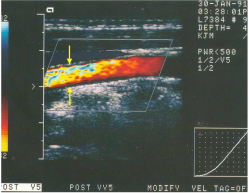

64.下圖為頸動脈之彩色都卜勒超音波,箭號所指可能為何? (A)正常且適當之參數設定 (B)彩色都卜勒之aliasing假影 (C)彩色都卜勒之side lobe假影 (D)彩色都卜勒之clutter假影